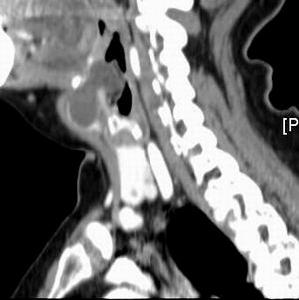

3.多見於小兒和青年。頸前舌骨平面下有圓形腫塊,表面光滑,界限清楚,囊性感,皮膚無粘連,隨吞咽上下移動。沿舌骨方向可觸及索狀物,張口伸舌時可覺腫塊回縮上提。

瘺管或囊腫X線碘油造影有助於明確診斷。但應與鰓裂囊腫、皮樣囊腫及異位甲狀腺相鑑別。